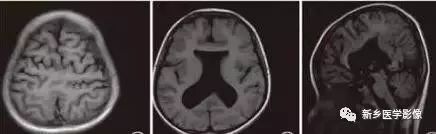

❶ 普遍性脑萎缩

普遍性脑萎缩常同时累及灰质和白质,可表现为双侧侧脑室扩大,而且是双侧侧脑室轻度对称性扩大最常见的原因。尤其多见于以脑白质萎缩为主的病人。

普遍性脑萎缩引起的侧脑室扩大通常比较对称,中线无移位。其特点是同时有脑沟、脑裂增宽等脑皮质萎缩的表现。

普遍性脑萎缩可见于正常老年人。

- 与年龄有关的脑萎缩:CT和MR检查可见脑室、脑池轻度扩大,脑沟轻度增宽,常以额叶和镰旁更明显。